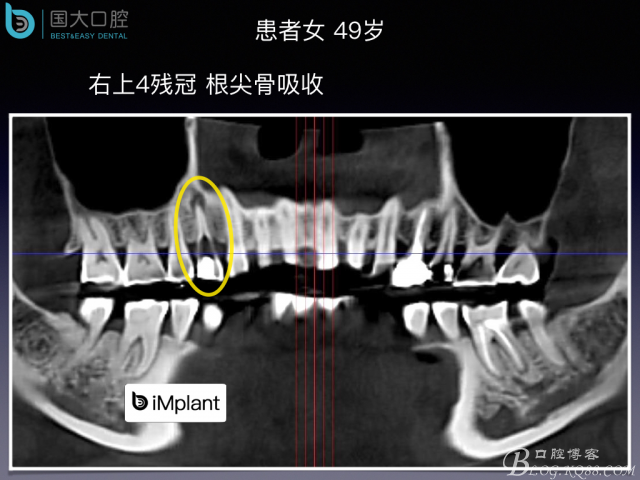

偏向顎側(cè)的即刻種植,應該如何修復?

20160820134224_22072.jpeg